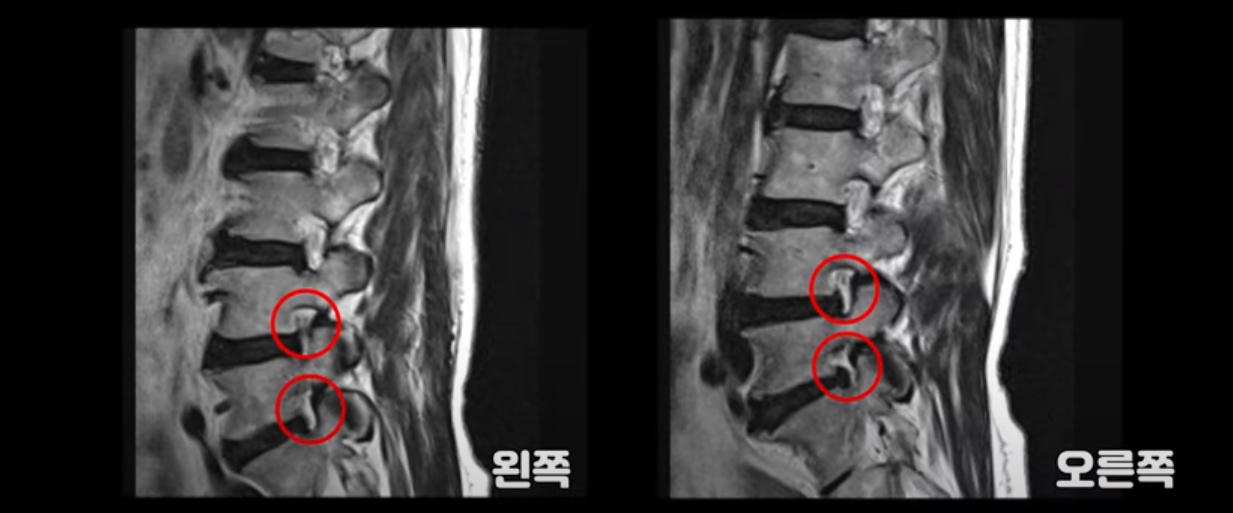

이 환자분 MRI 보면서 설명 드린 후 왜 이런 환자는 신경주사가 효과가 없는지 왜 근육재활치료를 꼭 받아야 하는지, 근육재활치료로 어떻게 좋아질 수 있는지 설명 드리도록 하겠습니다. 이분MRI를 보면 허리 여러 마디 퇴행이 진행되어 있고 디스크와 협착도 있지만 아주 심해 보이지는 않습니다.

이분 다리는 양쪽이 다 아픈데 양쪽 추공간이 좁아져 있긴 하지만 여전히 하얀 지방이 많이 보이는 상태로 심하게 좁아 보이지는 않습니다.